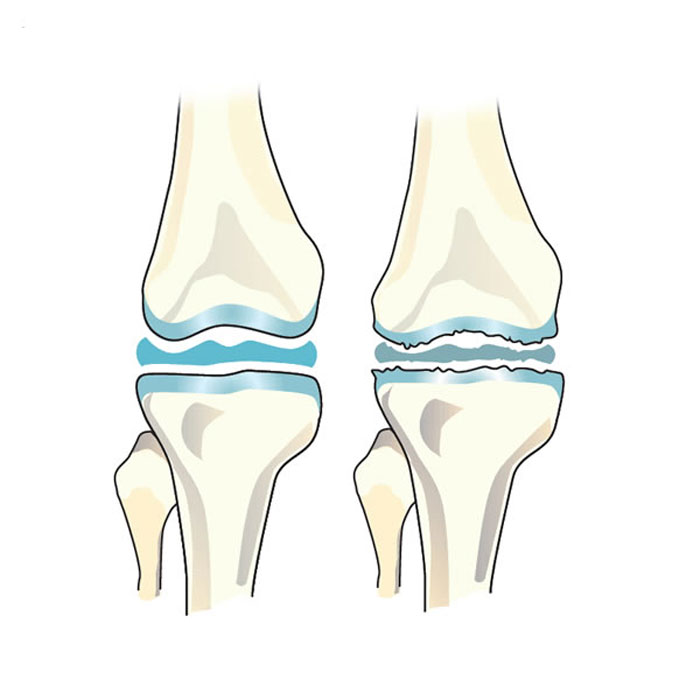

مفصل جایی است که دو استخوان بهم میپیوندند. انتهای این استخوانها با بافت محافظی به نام غضروف پوشانده شده است. آرتروز سبب تجزیه این غضروف میشود و باعث می شود استخوانهای مفصل به هم ساییده شوند. این مسئله میتواند باعث درد، سفتی و سایر علائم شود.

آرتروز (OA) شایعترین بیماری مفصلی مزمن (طولانیمدت) است. آرتروز یک بیماری پیشرونده با پنج مرحله از 0 تا 4 است. مرحله اول (0) مفصل طبیعی است. مرحله 4 نشاندهنده آرتروز شدید است. همه کسانی که آرتروز دارند تا مرحله 4 پیشرفت نمیکنند. این وضعیت اغلب مدتها قبل از رسیدن به این مرحله تثبیت میشود.

در افرادی که آرتروز شدید دارند، غضروف در یک یا چند مفصل از بین رفته است. اصطکاک استخوان بر روی استخوان میتواند علائم شدید زیر را ایجاد کند:

آرتروز زانو

آرتروز زانو که در محافل علمی و دانشگاهی بیشتر با نام استئوآرتریت و استئوآرتروز شناخته میشود، یک بیماری تخریبی پیشرونده در ناحیه مفاصل زانو است که علائمی همچون درد و محدودیتهای حرکتی را اعمال میکند.

این بیماری که شیوع آن در زنان بیشتر از مردان رخ میدهد را معمولاً با نام آرتروز پیری یاد میکنند؛ چرا که پیشرفت آن با افزایش سن بیمار افزایش پیدا میکند.

مانند آرتروز مفصل ران، آرتروز زانو نیز میتواند در یک یا هر دو زانو ایجاد شود. سن، ژنتیک و آسیبدیدگی زانو ممکن است در آرتروز زانو نقش داشته باشد.

درمان آرتروز زانو بستگی به مرحله بیماری دارد.

در این عارضه، مقداری از بافت غضروفی استخوانها در محل مفصل زانو تخریب میشود. این اتفاق موجب میشود استخوانها با فاصله کمتری نسبت به یکدیگر در فضایی با حداقل غضروف و حداکثر ساییدگی قرار بگیرند.

تداوم این وضعیت در بدن بیمار میتواند موجب بروز علائم آرتروز زانو شود.